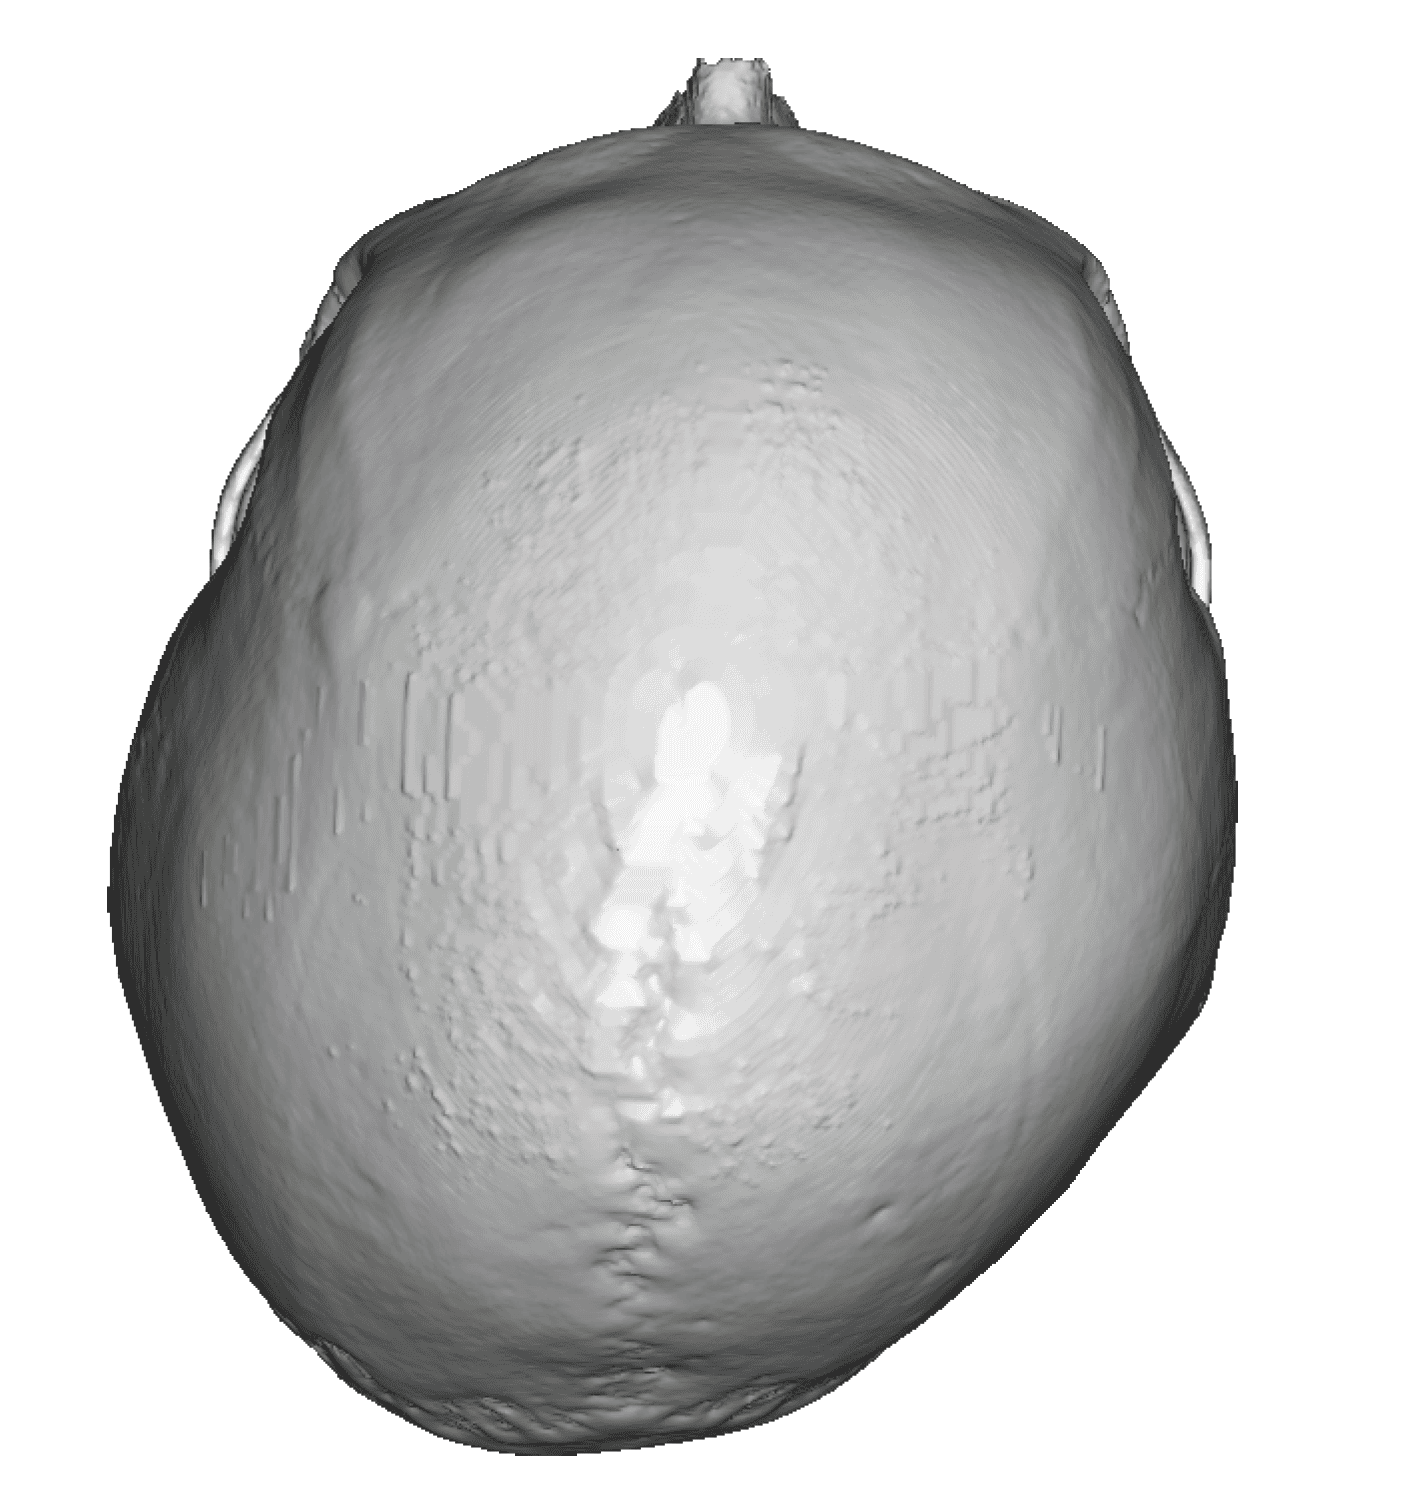

Patient 28

Desire for rounder shape to the top of the head from a congenital parasagittal deficiency skull shape.

Custom skull implant designed to fill in the parasagittal deficiencies.

Desire for rounder shape to the top of the head from a congenital parasagittal deficiency skull shape.

Custom skull implant designed to fill in the parasagittal deficiencies.